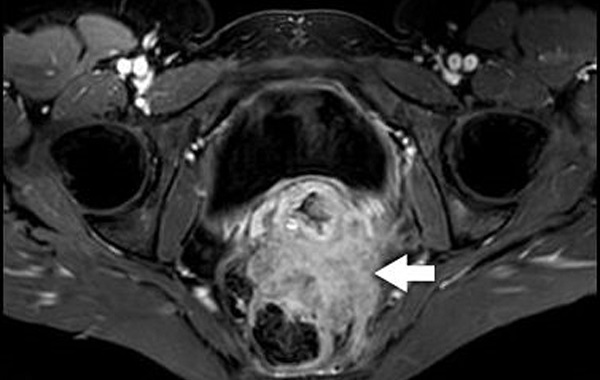

-v%C3%B9ng-ch%E1%BA%ADu-m%E1%BB%A5c-%C4%91%C3%ADch-v%C3%A0-c%C3%A1ch-th%E1%BB%B1c-hi%E1%BB%87n/chup-mri-vung-chau-phat-hien-ung-thu-co-quan-phu-khoa.jpg)

Chụp MRI vùng chậu phát hiện ung thư cơ quan phụ khoa